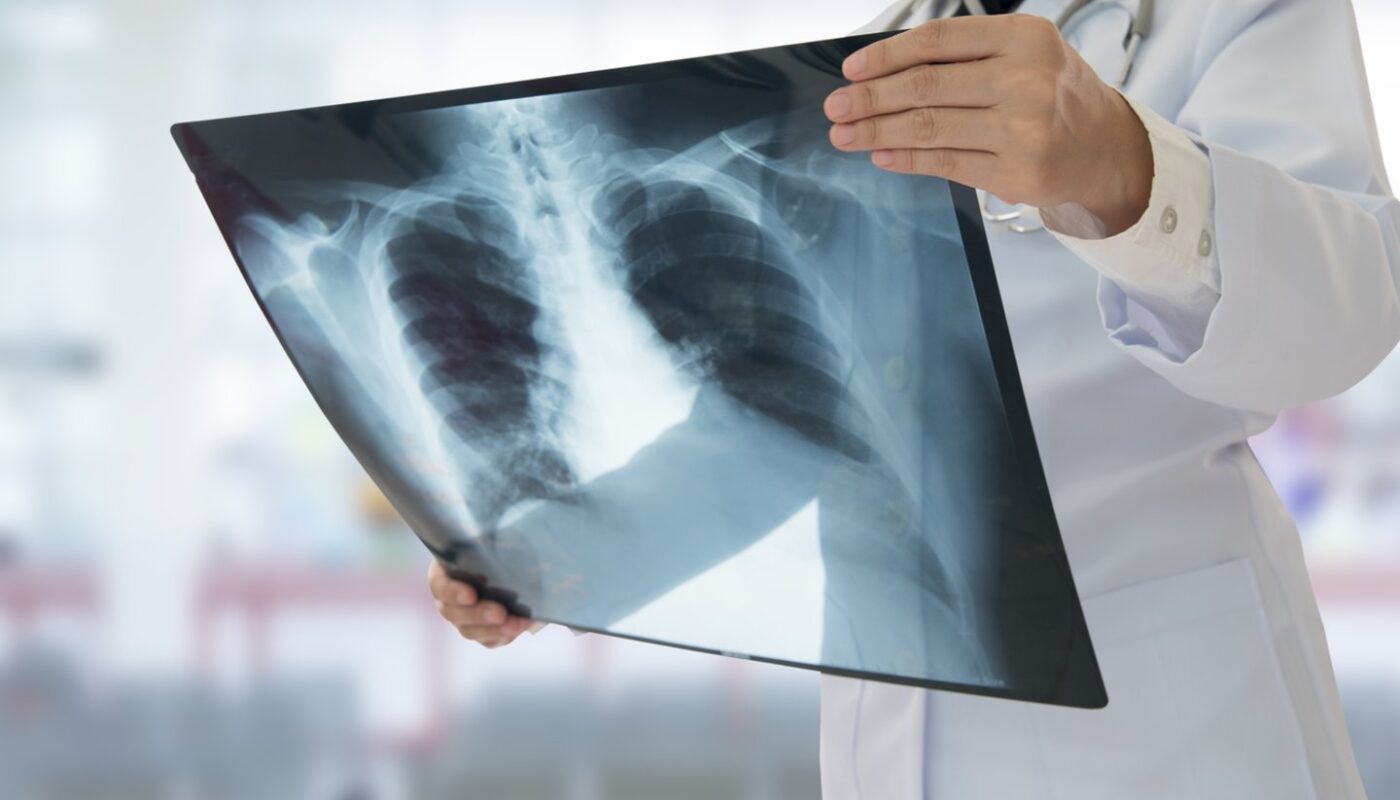

Atlikus krūtinės ląstos rentgenogramą, paaiškėjo nerimą keliantys pakitimai. Nuotraukoje buvo matyti, kad tarp dešinįjį plautį dengiančių audinių sluoksnių ir krūtinės ertmę išklojančių membranų susikaupė skystis. Šis skystis užpildė apatinio dešiniojo plaučio kvėpavimo takus, neleisdamas jiems tinkamai prisipildyti oro ir sukeldamas nuolatinį kosulį.

Norėdami tiksliau ištirti situaciją, medikų komanda atliko kompiuterinės tomografijos (KT) tyrimą. Rezultatai patvirtino blogiausias nuojautas – paciento dešinėje krūtinės pusėje aptikta didelė masė. Kaip vėliau nustatyta, darinys buvo tarpuplautyje – centrinėje krūtinės ertmės dalyje, kurioje glūdi gyvybiškai svarbūs organai, tokie kaip širdis, limfmazgiai, nervai ir kitos struktūros.